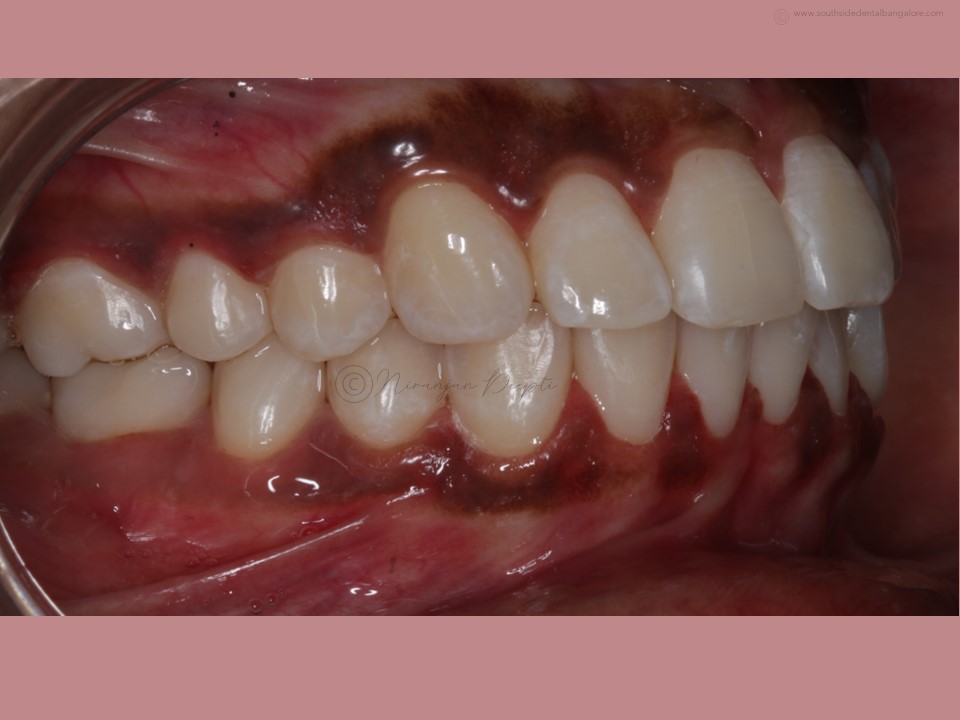

Polishing of teeth after the debonding of braces is a crucial step in the orthodontic treatment process.

- Smoother Surface: Braces leave adhesive residue and small imperfections on the tooth surface. Polishing helps smoothen these areas, reducing the risk of plaque accumulation and making it easier to clean teeth effectively.

- Minimizes Staining: Residual bonding materials and rough surfaces can attract stains, affecting the appearance of your smile. Polishing removes these stains and restores the natural luster of your teeth.

- Prevents Tooth Damage: Rough surfaces can cause friction against soft oral tissues, leading to irritation and potential damage. Polishing ensures that the teeth have a smooth surface, reducing the risk of irritation and discomfort.

- Enhances Aesthetics: Polishing creates a polished, uniform appearance, enhancing the overall aesthetics of your smile and boosting your confidence post-braces.

- Scaling: Before polishing, your orthodontist may perform scaling to remove any hardened plaque or calculus deposits that have accumulated during the braces treatment.

- Polishing: Using a specialized dental tool, your orthodontist/dentist will carefully polish each tooth surface to remove any remaining adhesive residue and smooth out imperfections.